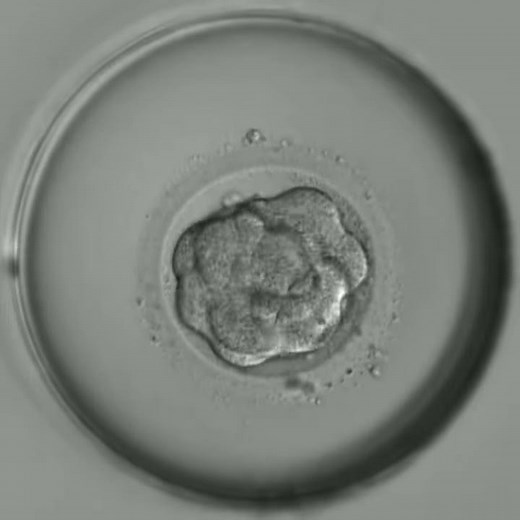

最新タイムラプス観察:受精から胚盤胞までの成長

視聴回数: 38.1万 回

2021年2月24日

YouTube

浅田レディースクリニック

受精卵の発育(~胚盤胞)

視聴回数: 17.8万 回

2018年3月27日

なかむらレディースクリニック